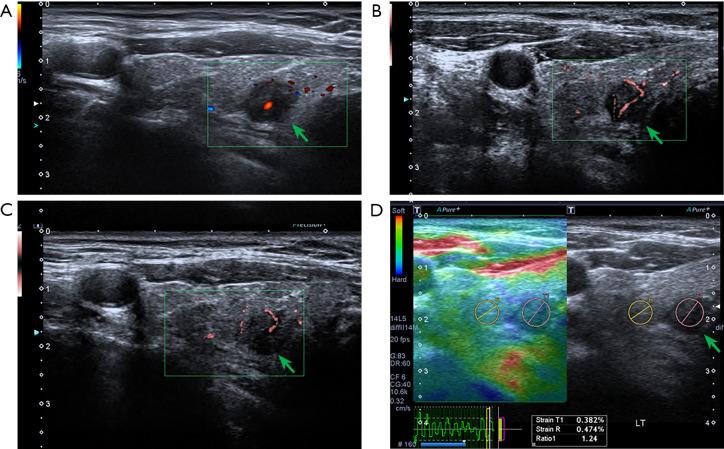

Tumor neovascularization and increased extracellular matrix stiffness have been confirmed to be crucial for oncology research, however, they are rarely integrated into diagnostic prediction models for predicting lateral cervical lymph node metastasis (LLNM). This study aimed to explore the correlation between these ultrasound parameters, clinicopathological characteristics and LLNM in papillary thyroid carcinoma (PTC), and construct a nomogram prediction model, as well as estimate its preoperative diagnosis values for LLNM.

METHODS

The clinical and ultrasound imaging data of 703 patients with postoperative histopathologically confirmed PTC were retrospectively analyzed. Conventional ultrasound, superb micro-vascular imaging (SMI) and strain ultrasound elastography (SUE) were performed for all patients, and they were stratified into training and validation cohorts based on the chronological sequence of surgery with a ratio of 7:3. Comprehensive evaluations of clinicopathological and ultrasonic features were conducted using least absolute shrinkage and selection operator (LASSO) regression and multivariate logistic regression, with the aim of identifying independent predictors of LLNM, and a nomogram prediction model was constructed. All LLNM patients were confirmed by postoperative pathology. Receiver operating characteristic curves (ROC) and calibration curves were drawn. Decision curve analysis (DCA) was performed to calculate the predictive efficiency, consistency, and clinical practicality of the model.

Among the 703 patients, 98 patients were diagnosed with LLNM (13.9%). According to the results of LASSO regression and multivariable logistic regression model, eight independent risk variables were screened to construct a prediction model, including sex, tumor size, multifocality, capsular invasion, microcalcification, perforator vessel, strain rate ratio (SRR) and ratio of metastatic central lymph nodes (LNR). The consistency index of the prediction model in the training cohort was 0.895, and it was 0.866 in the validation cohort. The optimal cutoff value (0.149) showed the balance between the sensitivity (80.6%) and specificity (84.5%). In both the training cohort and the validation cohort, the calibration curves were close to the standard curve, and the DCA curves showed that more than 90% of PTC patients could benefit from the prediction model.

CONCLUSIONS

Compared with conventional imaging modalities used alone, the integrated application of novel ultrasonographic technologies, including SMI and SUE, demonstrates superior diagnostic performance in predicting LLNM in PTC patients. This nomogram incorporating the aforementioned ultrasound parameters might be helpful for accurate preoperative risk stratification of LLNM, thereby assisting surgeons in formulating individualized surgical strategies prior to intervention.